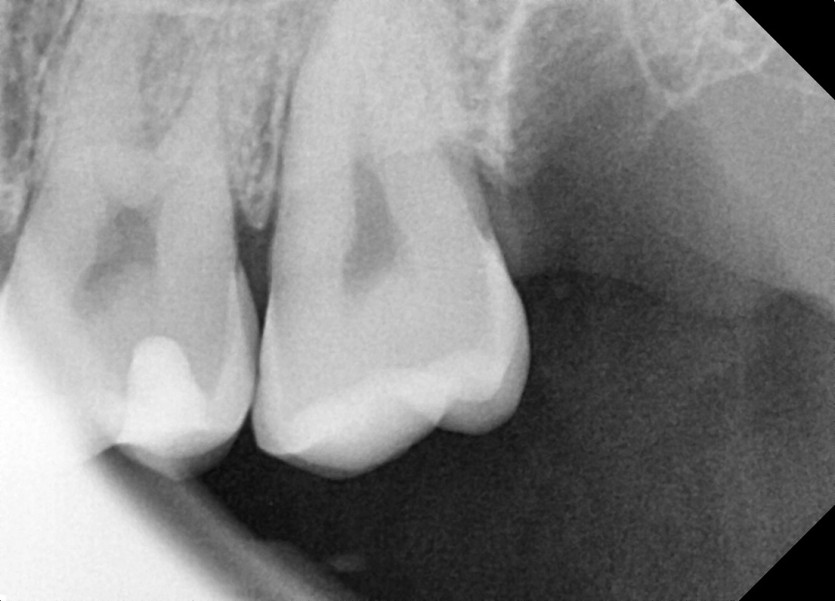

#18,28,38,48 사랑니 발치

구강 외과 전문의가 당일 발치했습니다.